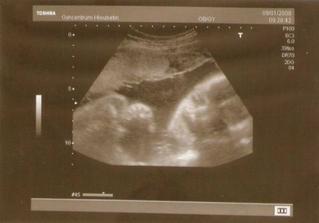

9.1.2008 - ultrazvuk, beruška na nás plazila jazyk, mrkala a polykala plodovou vodu 🙂 už je připravená hlavičkou dolů, váha 68 kg